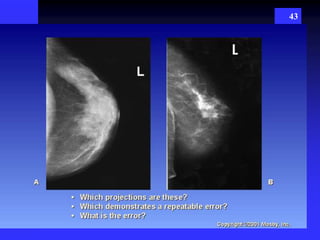

43

38 Routine Images - CC - cranio caudad  MLO – mediolateral oblique Additional view  “True” Lateral view  Latero-medial oblique view  Paddle compression view  Magnification view  Tangenital view  Cleavage view  Axillary view POSITIONING